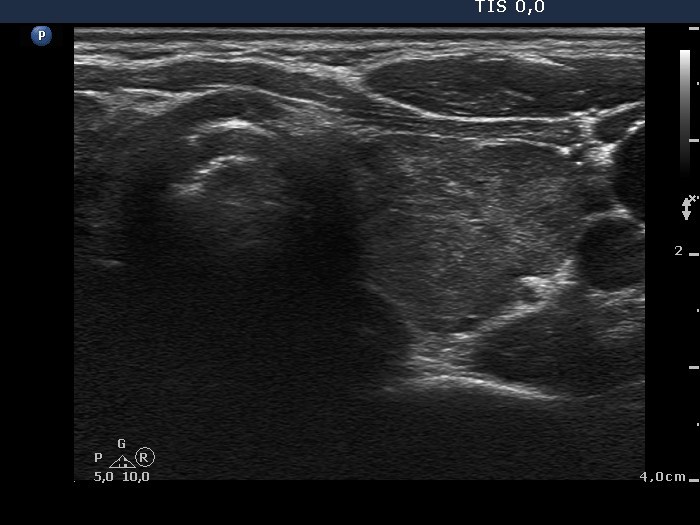

100 consecutive cases of papillary cancer - case 035

Present examination (ultrasonographic picture 8)

Left lobe, transverse scan. This lobe is moderately hypoechogenic and presents less hypoechogenic areas and various forms of hyperechogenic figures.